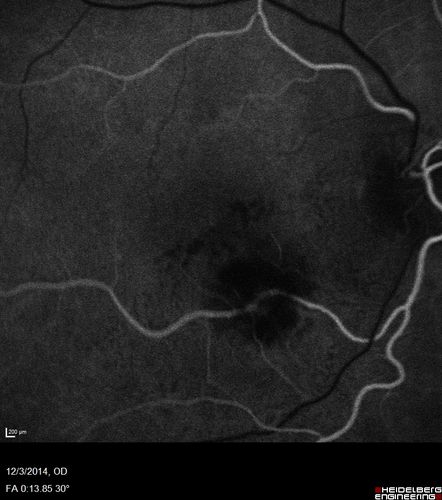

Macroaneurysm - Resolved without treatment

87 year old female with vision loss OD. Initial FA showed no leakage so no treatment was done and the fluid absorbed over 4 months. Initial VA 20/100, Final VA 20/80